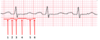

On an ECG, the QRS axis is -45 degrees.

Direction of QRS in Lead I:

Direction of QRS in Lead aVF:

What kind of deviation is this?

Direction of QRS in Lead I: Up

Direction of QRS in Lead aVF: Down

Left Axis Deviation

Which segments make up the PR interval?

1 + 2

Which segments make up the QT interval?

3 + 4 + 5

On an ECG, the QRS axis is +45 degrees.

Direction of QRS in Lead I:

Direction of QRS in Lead aVF:

What kind of deviation is this?

Direction of QRS in Lead I: Up

Direction of QRS in Lead aVF: Up

No deviation: 0 to +90 = normal ECG axis

Which ECG feature is labeled by segment 2?

PR Segment